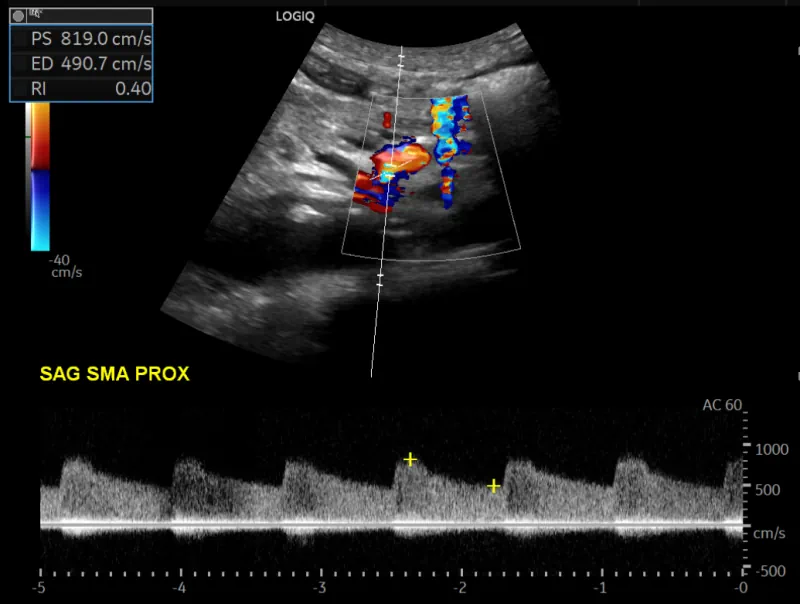

Usually, we start with a mesenteric artery ultrasound. On the one hand an ultrasound is safe and cheap. It also is sensitive at detecting elevated flow velocities in the arteries:

But it has two important disadvantages. First, image quality. You often cannot see the mesenteric arteries properly, either because of overlying bowel gas or just because. The second problem is clinical correlation. It is not uncommon for the velocity to be elevated, but in the end the patient does not really have stenosis.